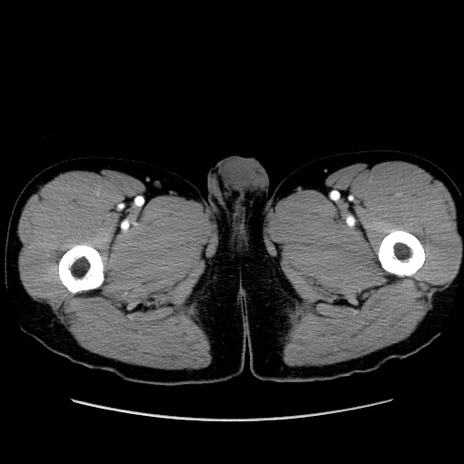

症例36(横断像)

【症例】20歳代 男性

【主訴】心窩部痛

【現病歴】今朝より上腹部痛あり。一旦軽快していたが再度出現したため救急要請。昨日夕に白身の魚を含む刺身を食べた。

【身体所見】BP 136/89mmHg、HR 74/min、BT 37.0℃、腹部:膨満、軟、心窩部に圧痛あり。反跳痛なし、筋性防御なし、腸雑音やや亢進あり。

【データ】WBC 17700、CRP 0.48